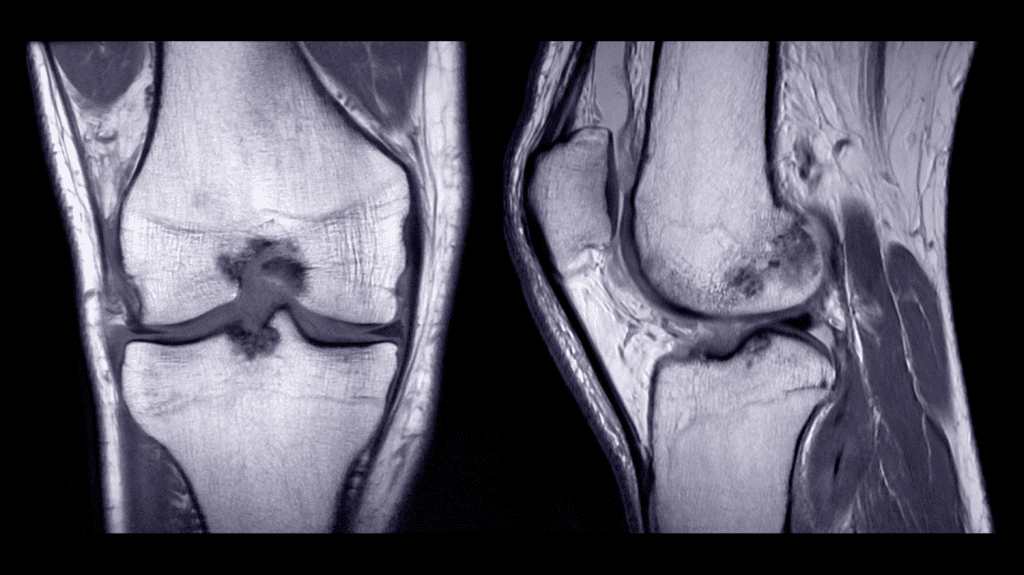

Magnetic Resonance Imaging (MRI): Detailed Soft Tissue Evaluation

MRI has changed how we diagnose arthritis. It lets doctors see soft tissue problems clearly. This makes MRI key for checking inflammatory arthritis.

Visualizing Synovitis, Effusion, and Bone Marrow Edema

MRI spots early signs of arthritis well. It finds synovitis, joint effusion, and bone marrow edema early. These signs can lead to serious damage if not treated soon.

- Synovitis detection shows inflammation in the joint lining.

- Joint effusion shows fluid build-up in the joint, a sign of inflammation.

- Bone marrow edema is an early sign of bone involvement in arthritis.

Contrast-Enhanced MRI for Inflammatory Arthritis

Using contrast agents in MRI makes inflammation easier to see. It highlights synovial enhancement, a sign of active inflammation. This helps doctors understand how active the disease is and how far it has spread.